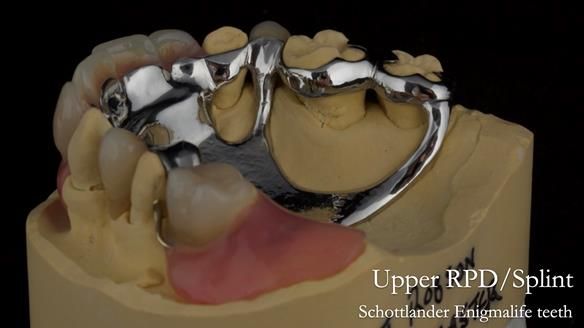

In this edition, I present the removable partial denture treatment for Jean, an 80-year-old woman with a sore mouth caused by a soft tissue-supported 'gum stripper' acrylic denture and a clenching habit. Below, I outline the step-by-step process of her treatment. It wasn't straightforward; I had to remake the denture after it fractured to achieve a satisfactory result. Each patient is unique, and sometimes a new RPD serves as a prototype. Occasionally, I need to make adjustments, learn from any mistakes, and refine the design to get it right.

The treatment has been a success over the past 4 years.